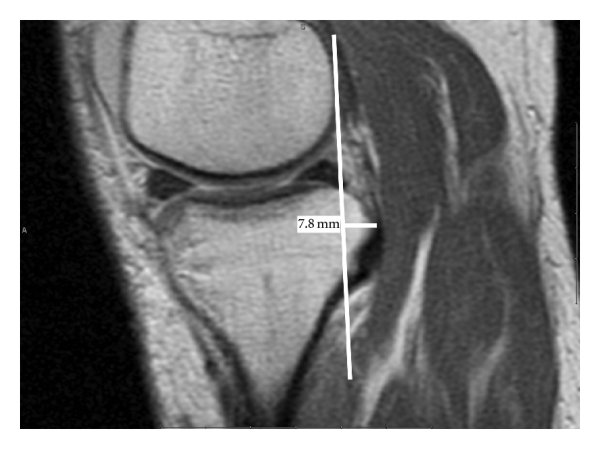

All images were performed on a 1.5 T magnet, using our institutional standard knee MRI protocol. Sagittal PD and fat suppressed T2-weighted fast spin-echo imaging, coronal T1-weighted and fat suppressed T2-weighted fast spin-echo imaging and axial T2-weighted fat suppressed FSE imaging sequences were acquired. Images were obtained with the knee in passive extension. Measurements were performed from the sagittal PD images using the method described by Vahey et al. [2, 3]. Measurements were performed in the midmedial and midlateral compartments independently by two musculoskeletal fellowship trained radiologists for all patients and 18 of 22 controls. On the sagittal image, a tangential line was drawn posterior to the femoral condyle, and another similar line was drawn posterior to the tibia plateau. Perpendicular measurements of the relative anterior or posterior translation were made (Figure 1) for each knee.

(a)

(b)

(c)